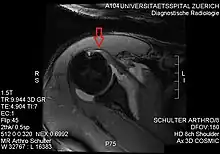

Imaging

There is no singularly imaging device or technique for a satisfying and complete subscapularis examination, but rather the combination of the sagittal oblique MRI / short-axis US and axial MRI / long-axis US planes seems to generate useful results. Additionally, lesser tuberosity bony changes have been associated with subscapularis tendon tears. Findings with cysts seem to be more specific and combined findings with cortical irregularities more sensitive.[5]

Another fact typically for the subscapularis muscle is the fatty infiltration of the superior portions, while sparing the inferior portions.

Since the long biceps tendon absents itself from the shoulder joint through the rotator cuff interval, it is easily possible to distinguish between the supraspinatus and the subscapularis tendon. Those two tendons build the interval sling.